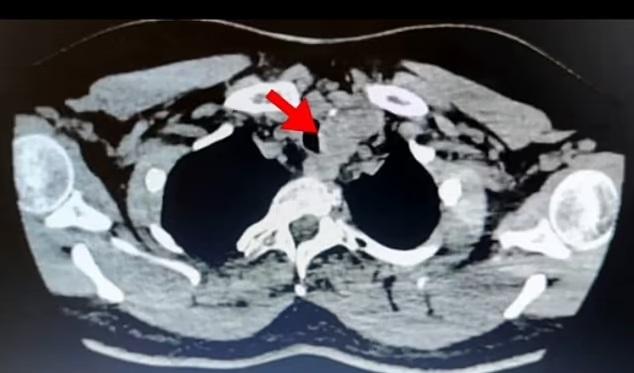

馬來西亞一名54歲女子持續咳嗽6個月,最後甚至咳出血,她這時才求醫。醫生為她染血又沒有感染或異常,其他檢查也沒有任何發現,最後從腹部至頸部做電腦掃描,發現甲狀腺(thyroid gland)擴大,再用支氣管內窺鏡超聲波檢查,終於找到「原兇」——甲狀腺有凸起物體,切片化驗後證實屬惡性腫瘤,診斷患了乳頭狀甲狀腺癌(papillary thyroid cancer)。

醫生觸摸該名患者頸部並未發現腫脹或腫塊,檢查顯示甲狀腺功能亦正常。連串檢測都找不到原因,最後做電腦掃描和超聲波檢查才發現甲狀腺擴大並局部壓著氣管,以及有很多小瘤,而小瘤有鈣化細點,是癌症明顯徵狀。鑑於腫瘤的體積大,並懷疑癌細胞已擴散到附近周圍,那名女患者需切除整個甲狀腺。在手術後,該病人亦需接受兩輪放射治療。甲狀腺位於頸前方,負責調節身體的新陳代謝,分泌荷爾蒙控制身體使用能量的速度和製造蛋白質等。